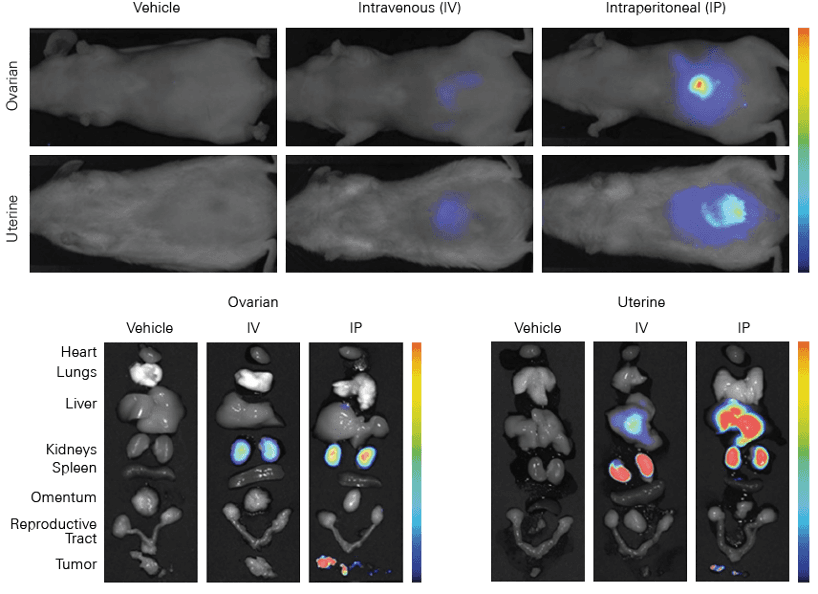

Figure 1. IRDye 800CW EGF imaged 96 h post injection. Image was captured with the Pearl Imager with pseudo-color representing the signal in the 800 nm channel overlaid on the mouse white light image. Research conducted at LI-COR Biosciences.